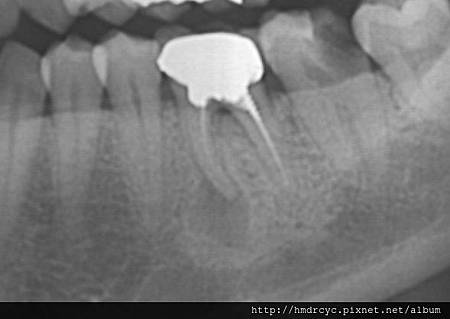

牙根斷裂是牙齒的絕症

斷裂後通常會有咬痛 腫包

牙根可以探到裂痕 但假牙包住的部分則較難發現

若假牙底下支撐的牙齒斷裂

那唯一的治療方式就只有拔除了

斷裂處的發炎會日漸吸收周圍的骨頭

若硬撐著不拔 最後牙肉骨頭都會過度破壞